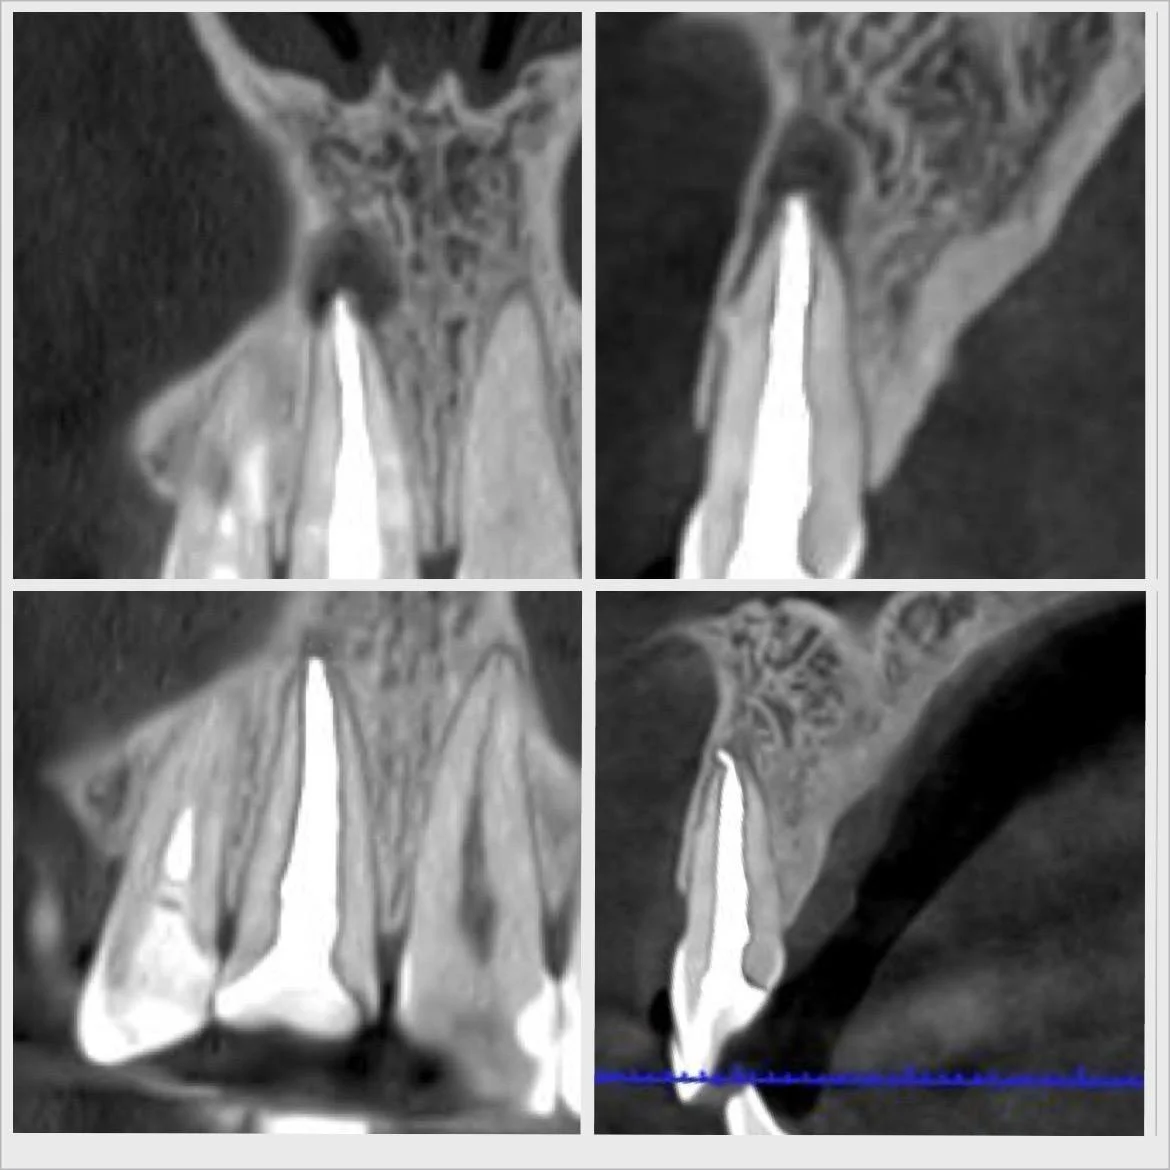

Efekty leczenia